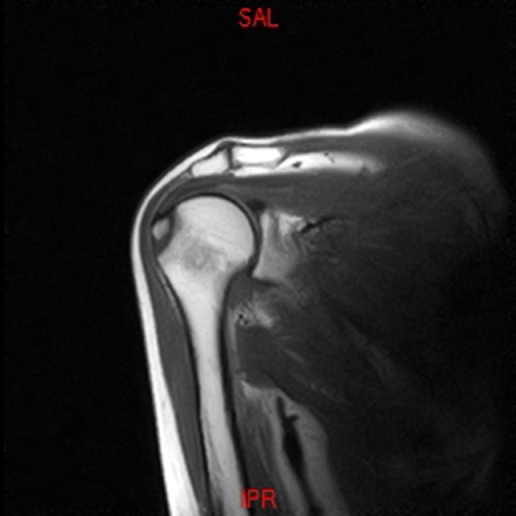

• RESONANCIA NORMAL HOMBRO COR T1